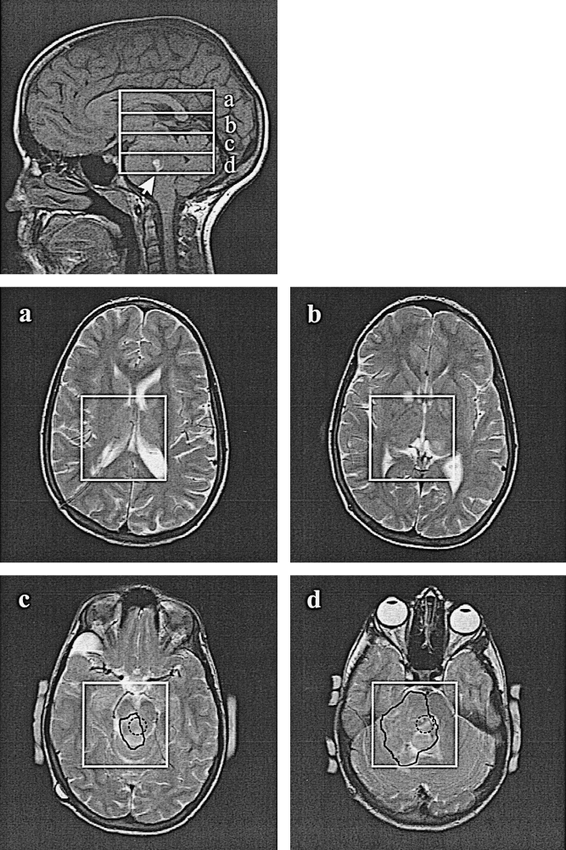

The MR images and MR spectra from two studies are presented in Figures 2 through ⇓⇓5. The PRESS box and HSI partitions, a through d, are superimposed on the sagittal images, Figures 2 and 4, and the axial MR images from the center of each HSI slice. A neuroradiologist traced the FASI on the images before seeing the MR spectra. The proton spectra from HSI slices a through d of Figures 2 and 4 are shown in Figures 3 and 5, respectively. In each case, the spectra from the voxel(s) corresponding to the glioma on the MR images in Figures 2 and 4 are indicated by dashed, shaded circles. Note that these regions yield a high Cho:Cr>2 ratio, which is typical of tumors in children and adults (8, 28–31). Regions of elevated 2>Cho:Cr>1.3, which extend much farther then the tumorlike voxel(s) in each patient, were shaded by a spectroscopist before seeing the FASI outline on the MR image.

Top, Sagittal image shows the placement of the 6 × 6 × 6-cm PRESS VOI, the four 1.5-cm-thick HSI slices, a–d, and the chiasmal glioma (arrow) in a 3-year-old boy.

a–d, Axial T2-weighted images (FOV = 22 cm) of the corresponding HSI slices, superimposed with the axial projection of the 6 × 6-cm VOIs. The FASI regions were marked with a solid black line by a neuroradiologist. The dotted circle in d indicates the location of the glioma.

Top, Sagittal image superimposed with the 6 × 6 × 6-cm PRESS VOI, the four 1.5-cm-thick HSI slices, a–d, and the brain stem glioma in an 11-year-old girl (arrow).

a–d, PRESS VOIs and FASI regions are marked with a solid black line on the corresponding axial T2-weighted images (FOV = 22 cm) from slices a–d. The dotted circles on axial images c and d indicate the location of the glioma.